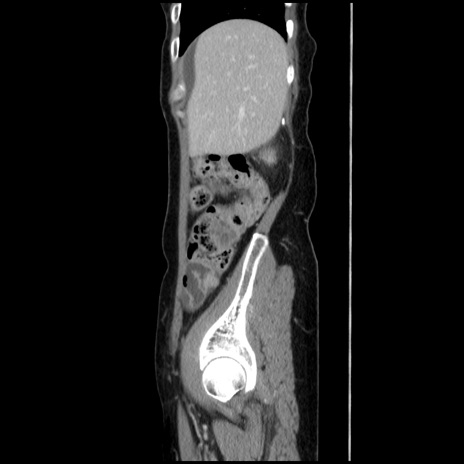

症例32(矢状断像)

【症例】40歳代 女性

【主訴】上腹部痛、嘔気・嘔吐

【現病歴】約9時間前頃から急に上腹部痛、嘔気、嘔吐が出現。改善しないため救急要請。

【既往歴】子宮頚癌(広汎子宮全摘術、放射線療法)、腸閉塞

【身体所見】腹部:平坦、軟、腸雑音亢進、上腹部を中心に腹部全体に圧痛あり。

【データ】WBC 8400、CRP 0.03